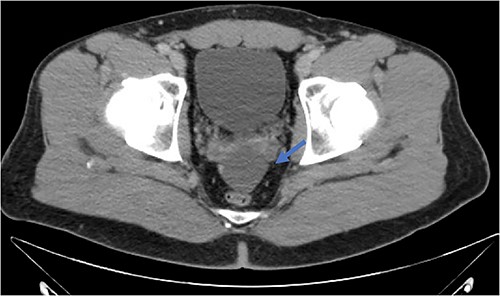

Low-grade appendiceal mucinous neoplasm (LAMN) is a rare entity present in ~1% of appendectomies [1, 2]. It is described by the World Health Organization (WHO) as one of three main categories of mucinous neoplasms: mucinous adenoma, LAMN, and appendiceal adenocarcinoma. The features of LAMN include acellular or cellular extra-appendiceal mucin, and there is a predisposition for female patients over 50 years of age [2–4]. If left untreated, sequelae include rupture of the appendix and mucocele with potential progression to pseudomyxoma peritonei. This is associated with high morbidity and mortality [1–4]. The clinical presentation of LAMN can be quite variable. Some patients are asymptomatic with the lesion incidentally identified during imaging or other operative procedures, while other patients may present with abdominal pain, weight loss, and acute appendicitis. In advanced disease, there may be the presence of pseudomyxoma peritonei, abdominal distension, and abdominal hernia [5–7]. Thus, imaging is an important tool in diagnosis and management. Computerized tomography (CT) is particularly useful when identifying legions in the ileocecal region, as it offers multi-planar, high-definition anatomic evaluation of the intra-abdominal contents [8]. LAMN, if ruptured, may appear on CT as fluid collections with a similar density to water in the absence of visualization of the appendix as a separate structure or evidence of active inflammation (Fig. 1). In this report, we describe a case of LAMN initially presumed to be appendicitis without the classic of an acute inflammatory process ultimately treated with surgical resection. We also review the available literature regarding the presentation, diagnosis, and management of LAMN.

Fluid collection is present in the expected location of the appendix that measures 5.2 × 2.9 × 6.6 cm (blue arrow). The appendix is not seen as a separate and distinct structure.